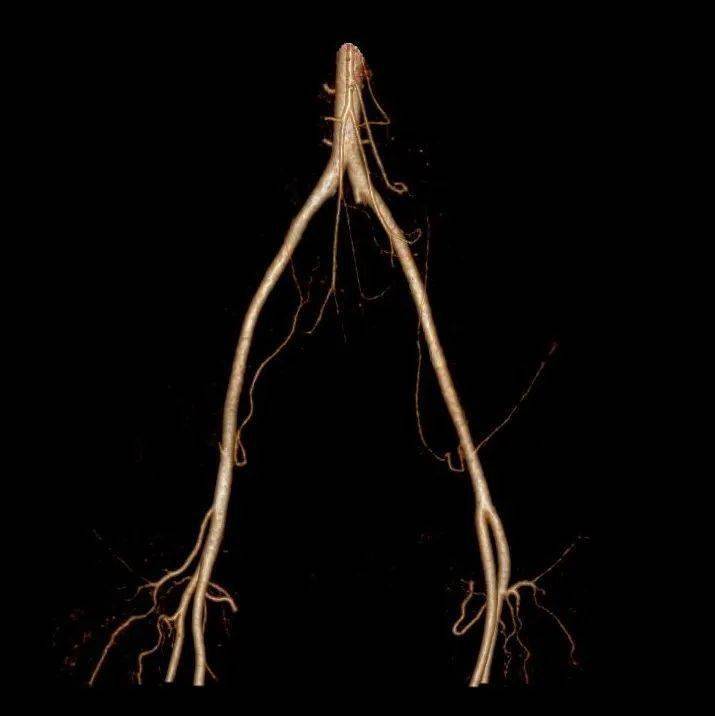

04 大范圍快速血管成像 “魚和熊掌”可以兼得

全身各部位血管造影成像,準確了解血管及相關臟器的形態結構,評估血管及臟器功能,準確判斷出血、栓塞、血管瘤、血管畸形、血管狹窄、腫瘤供血等情況。

腹主動脈瘤伴附壁血栓